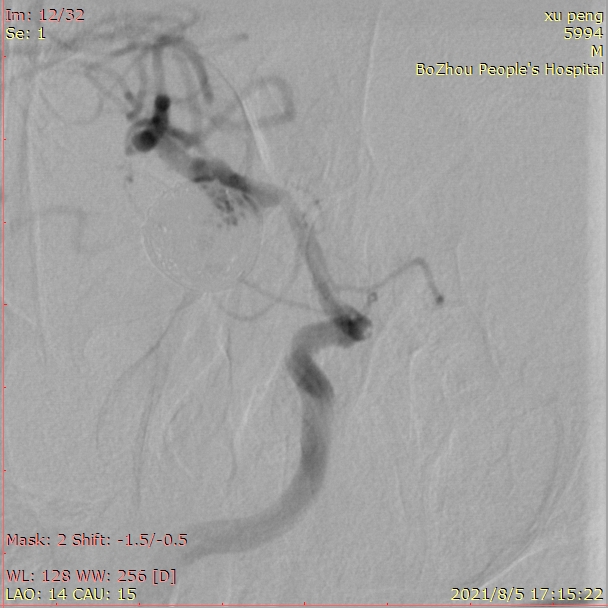

观察15分钟后再次造影,正位片。

观察15分钟后再次造影,侧位片。

载瘤动脉通畅,手术结束。

术后患者带气管插管回病房,次日病人神志清楚,四肢活动自如。